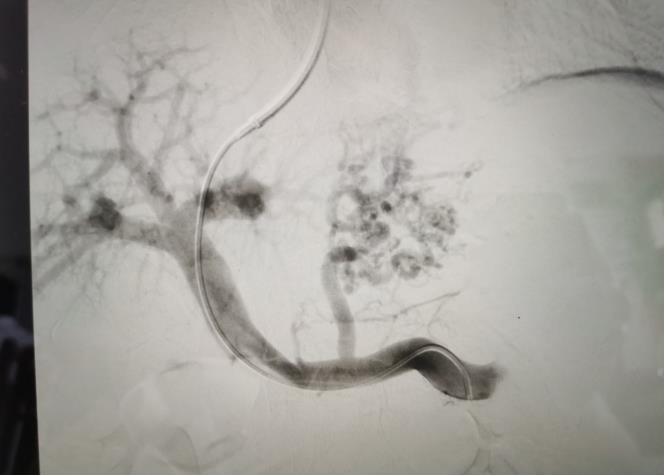

經(jīng)過我院血管介入科醫(yī)療團(tuán)隊(duì)的精心準(zhǔn)備,患者在數(shù)字減影血管造影機(jī)(DSA)導(dǎo)引下,順利經(jīng)頸靜脈入路進(jìn)入下腔靜脈并成功穿刺了門靜脈右支主干,術(shù)中栓塞了曲張的胃冠狀靜脈-食管靜脈叢將支架植入肝實(shí)質(zhì)內(nèi),支架兩端分別置于門靜脈和肝靜脈內(nèi),術(shù)程歷時(shí)2小時(shí),術(shù)中患者時(shí)刻保持清醒,手術(shù)切口僅5毫米,術(shù)后第2天恢復(fù)飲食,腹脹、腹水癥狀明顯好轉(zhuǎn),未出現(xiàn)嘔血、黑便及肝性腦病等并發(fā)癥,術(shù)后第3天康復(fù)出院。